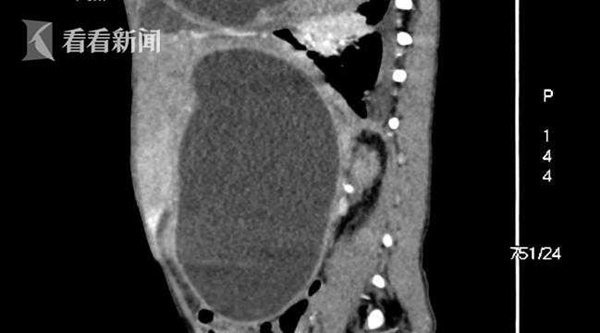

Bác sĩ Vương Kiến Nghiêu, khoa ngoại, bệnh viện Shenzhen Children's Hospital, cho biết: "Kết quả chụp CT cho thấy vùng bụng và ngực của bệnh nhi có 2 u nang lớn. Đặc biệt u nang vùng ngực có kích thước rất lớn đã chèn ép phổi bên phải. Kết quả xét nghiệm máu cho thấy, bệnh nhi mắc bệnh sán chó hay còn gọi là sán kim. Nang sán chứa hàng triệu đầu sán. Nếu nang sán vỡ, sẽ phóng thích hàng triệu đầu sán non theo máu ký sinh khắp nơi trên cơ thể như phổi, gan, lách, não, gây ra sự nhiễm độc, khiến việc phẫu thuật trở nên khó khăn".